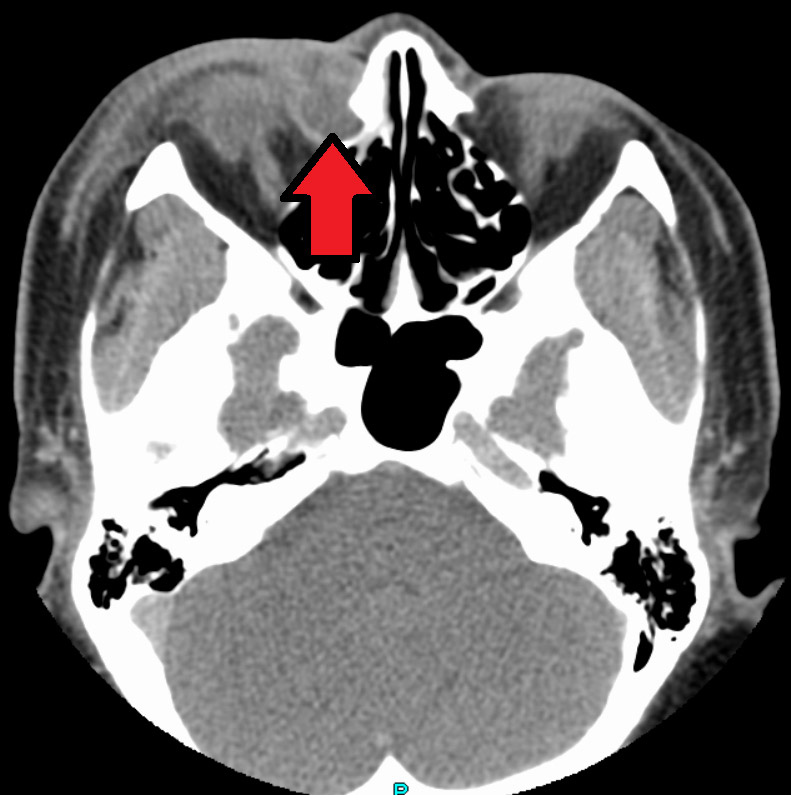

Dacryocystitis is an infection of the tear sac that lies between the inner corner of the eyelids and the nose. It usually results from blockage of the duct that carries tears from the tear sac to the nose.

Detection and Diagnosis

Image by James Heilman, MD – Own work, CC BY-SA 4.0,

https://commons.wikimedia.org/w/index.php?curid=59655169